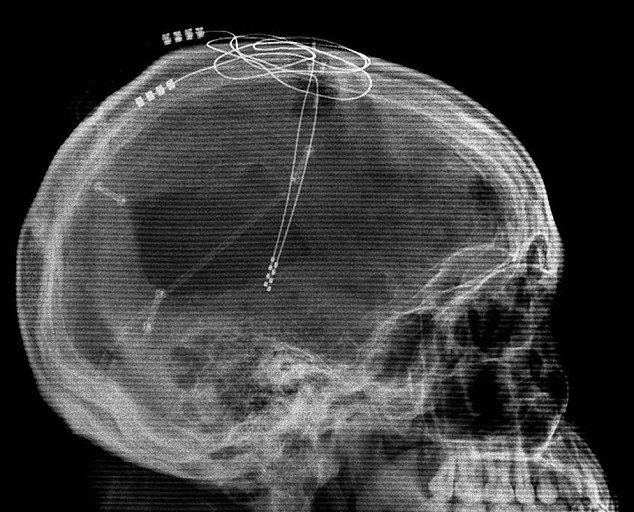

دستگاه ضربان ساز مغزی سلول‌های آلزایمری را دوباره جوان می‌کند

به گزارش فرهنگ عجب شیر به نقل از خبرنگاران؛ کارشناسان به  نوعی درمان منحصر به فرد و جدید در خصوص مبارزه با زوال عقل دست یافته‌اند که در  نوع خود بی‌نظیر است. گفتنی است؛ این درمان شامل استفاده از یک دستگاه ضربان ساز pacemarker و قرار دادن آن در مغز است که سبب تشکیل و فرم گیری سلول‌های جدید مغزی …